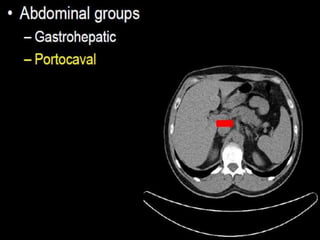

CT cross sectional anatomy.